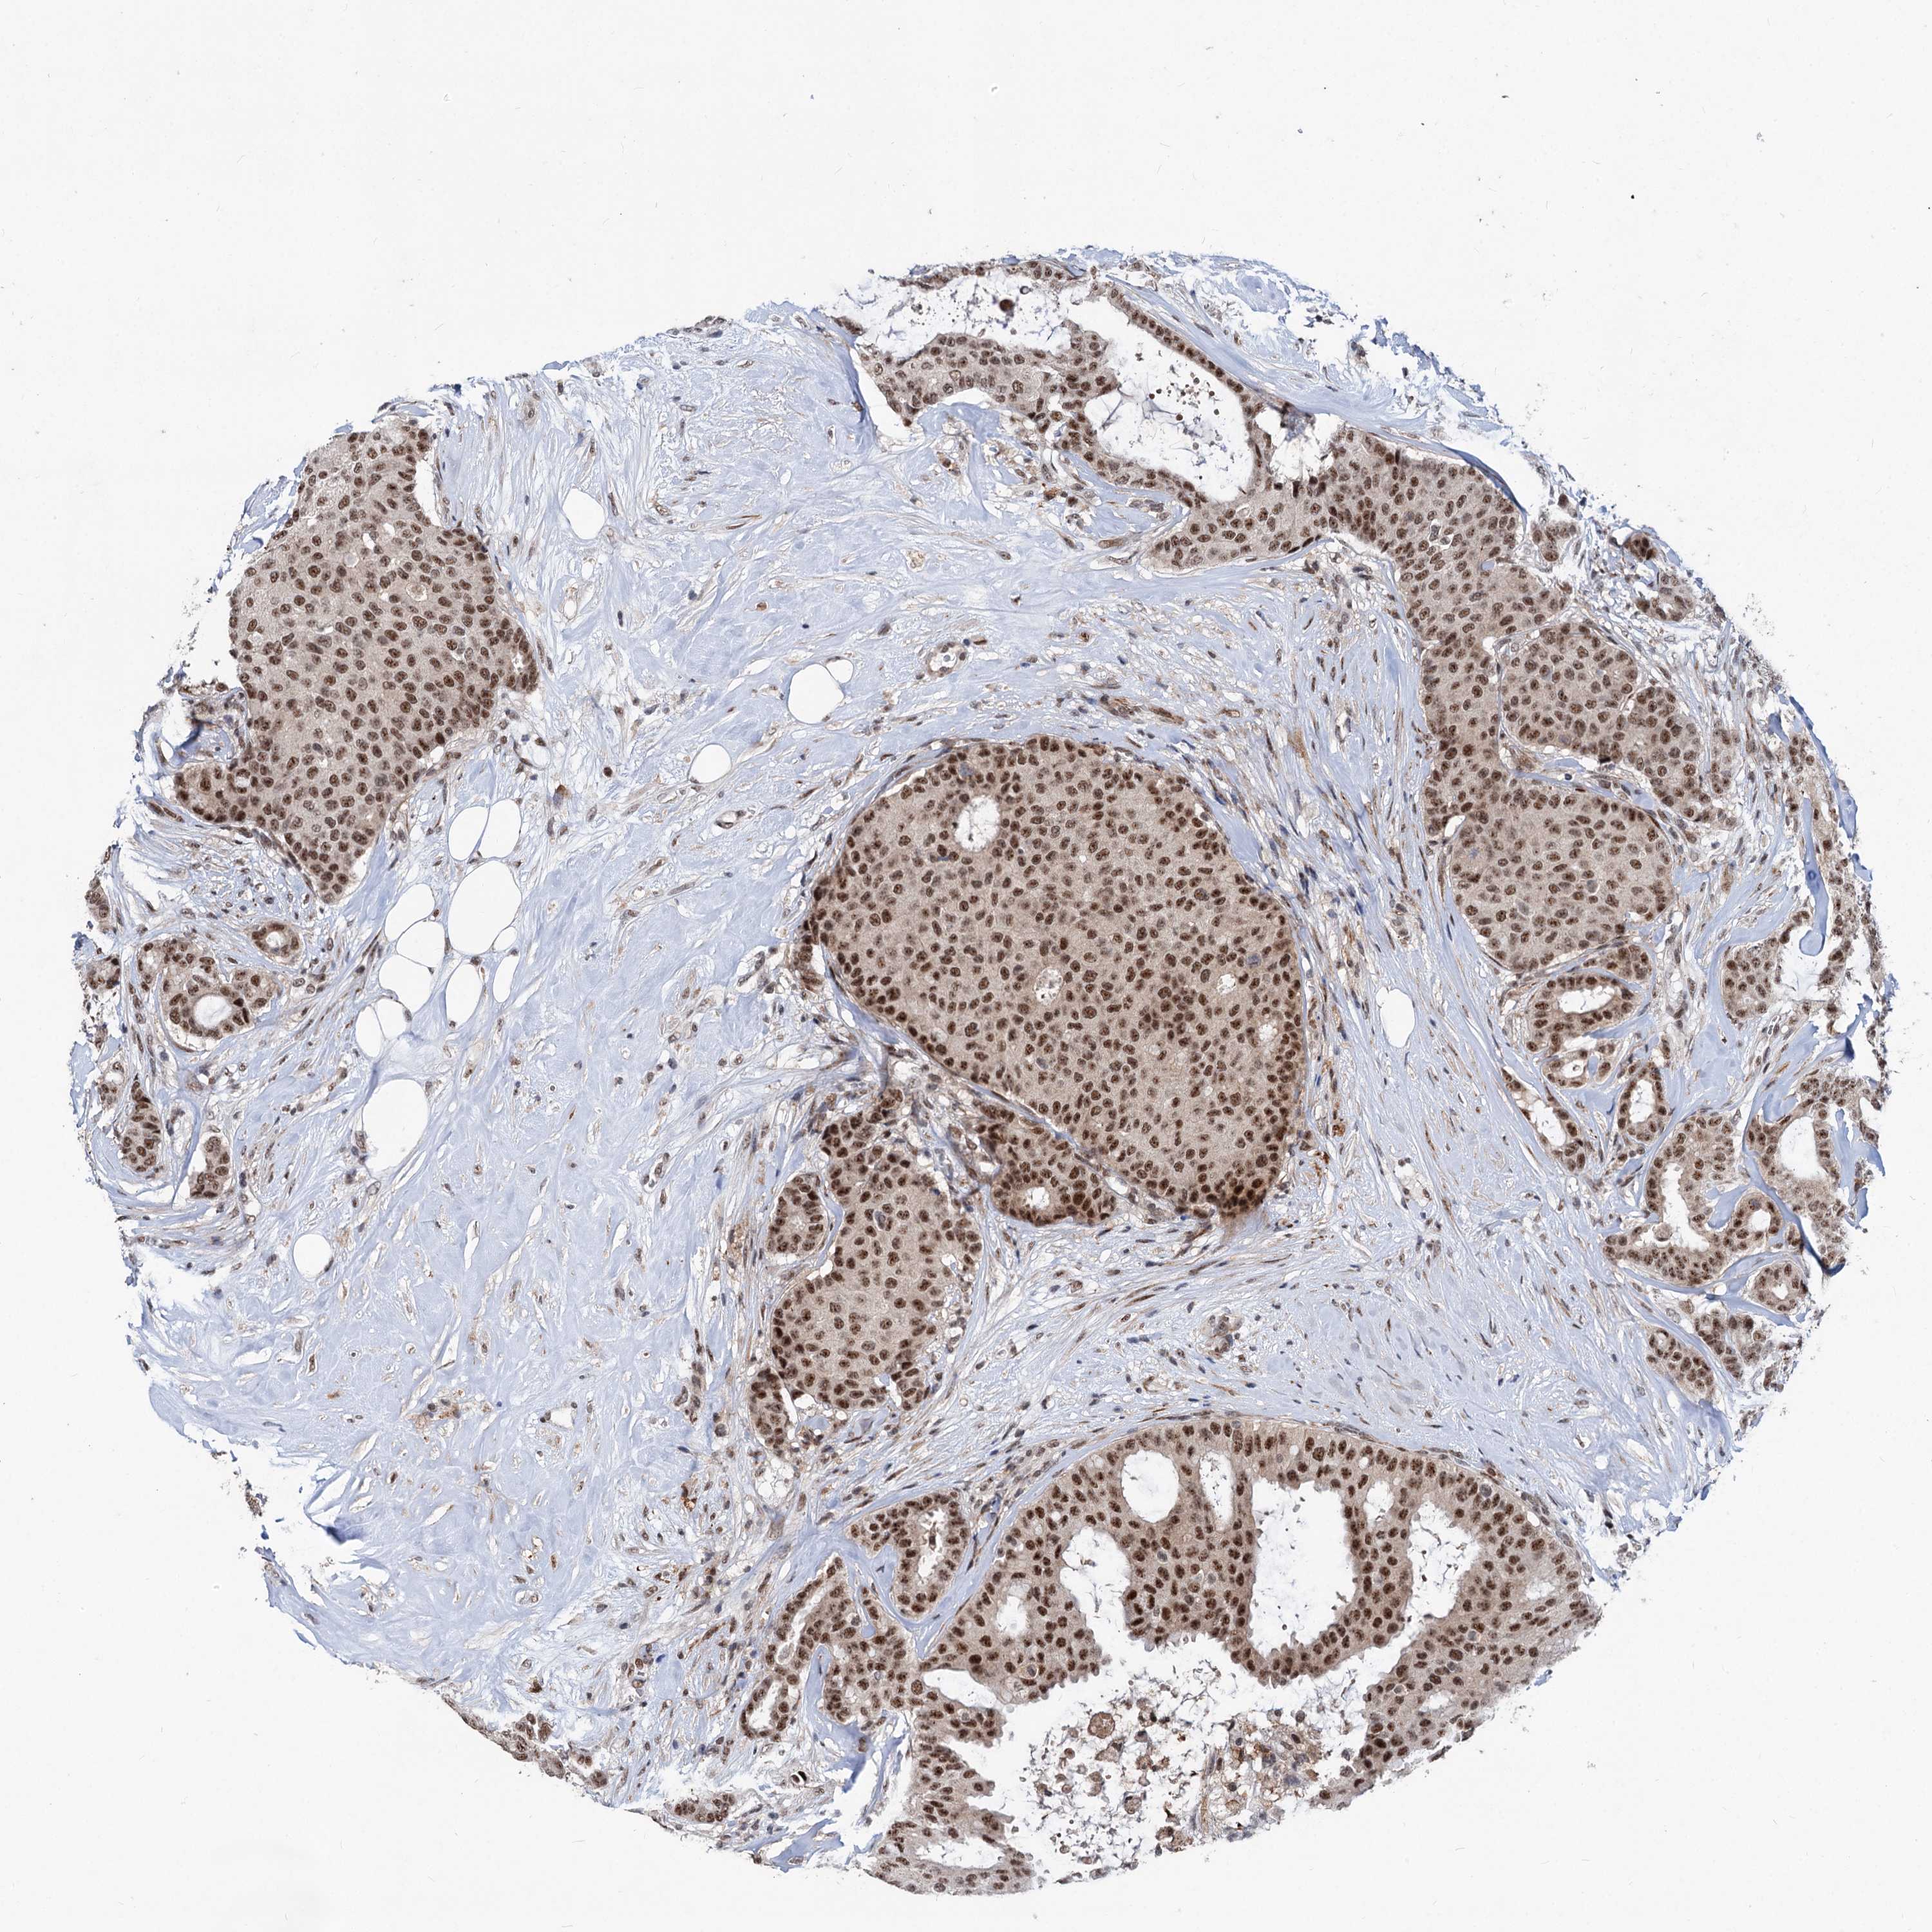

CANCER BREAST CANCER Show tissue menu

BRCA TCGA BRCA VALIDATION PROTEIN EXPRESSION